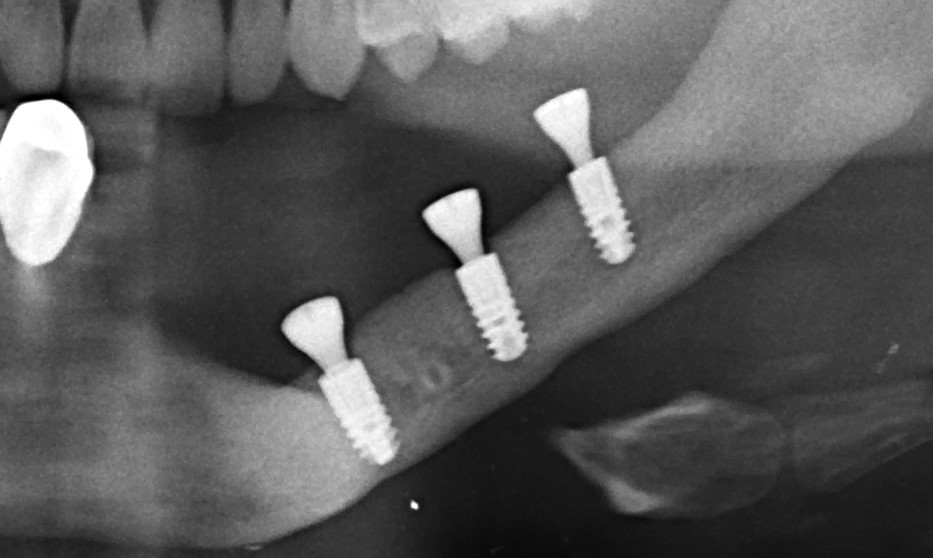

- компьютерная томография, поскольку это единственный способ объективно оценить биотип и измерить линейные параметры участка челюстной кости: